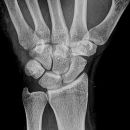

Handgelenk a.p.

Beurteilungskriterien

• Neigung der distalen Radiusgelenkfläche in der Frontalebene: 15 – 35°

• Längenverhältnis Radius – Ulna: Proc.styloideus radii überragt Gelenkfläche der Ulna um 9 –12mm (<9mm Ulna-Plusvariante, >12mm Ulnaminusvariante)

• Kontinuität der drei Karpalbögen:

Proximaler Bogen: proximale Gelenkflächenkonturen von Scaphoid, Lunatum und Triquetum

Mittlerer Bogen: distale Gelenkflächenkonturen von Sacphoid, Lunatum und Triquetum

Distaler Bogen: proximale Gelenkflächenkonturen von Capitatum und Hamatum

Fehlende Abgrenzbarkeit, Versatz oder Unterbrechung sind als pathologisch zu bewerten und deuten auf eine Luxation hin.

Trapezförmige Darstellung des Lunatum in Neutralstellung? Augenzeichen des Hamulus? Superposition von Pisiforme und Triquetum? Metacarpale III in Projektion innerhalb der Radiusgelenkfläche? Lunatum zu >50% über Radiusgelenkfläche? Cave: bei Radial- oder Ulnarduktion wandert das Lunatum in umgekehrter Richtung.

• M-förmiger Verlauf der Gelenkspalten der Carpometacarpalgelenke? Luxationsstellung in den Carpometacarpalgelenken (meist dorsale Luxation)?

• Gelenkspaltweiten des Radiocarpalgelenk 2 – 2,5mm, der Carpometacarpalgelenke 1 –2mm, distales Radioulnargelenk 2mm, Gelenksspaltweiten der Intercarpalgelenke 1,5 – 2mm

Cave: SL-Dissoziation (Ruptur des SL- Bandes, häufigste Gefügestörung): Terry-Thomas-Sign = SL-Spalt > 3mm, Siegelringzeichen = Ringförmige Transparenzminderung im mittleren Scaphoiddrittel durch orthograde Projektion der Taille infolge Rotation.

• Obliteration des Scaphoidfettstreifens?

• Täuschungsmöglichkeiten durch Vielzahl akzessorischer Ossikel (abgerundete, zirkulkär-geschlossene Kortikalis), geteilte Handwurzelknochen (Scaphoid, Lunatum, Pisiforme) und Gefäßkanälchen

• Target areas leicht zu übersehender Frakturen: distales Radioulnargelenk, Processus styloideus radii et ulnae, Basen der Metacarpalia (v.a. MCP I), Hamulus.

• Grundsätzlich gilt: unklare Verhältnisse ->CT-Indikation